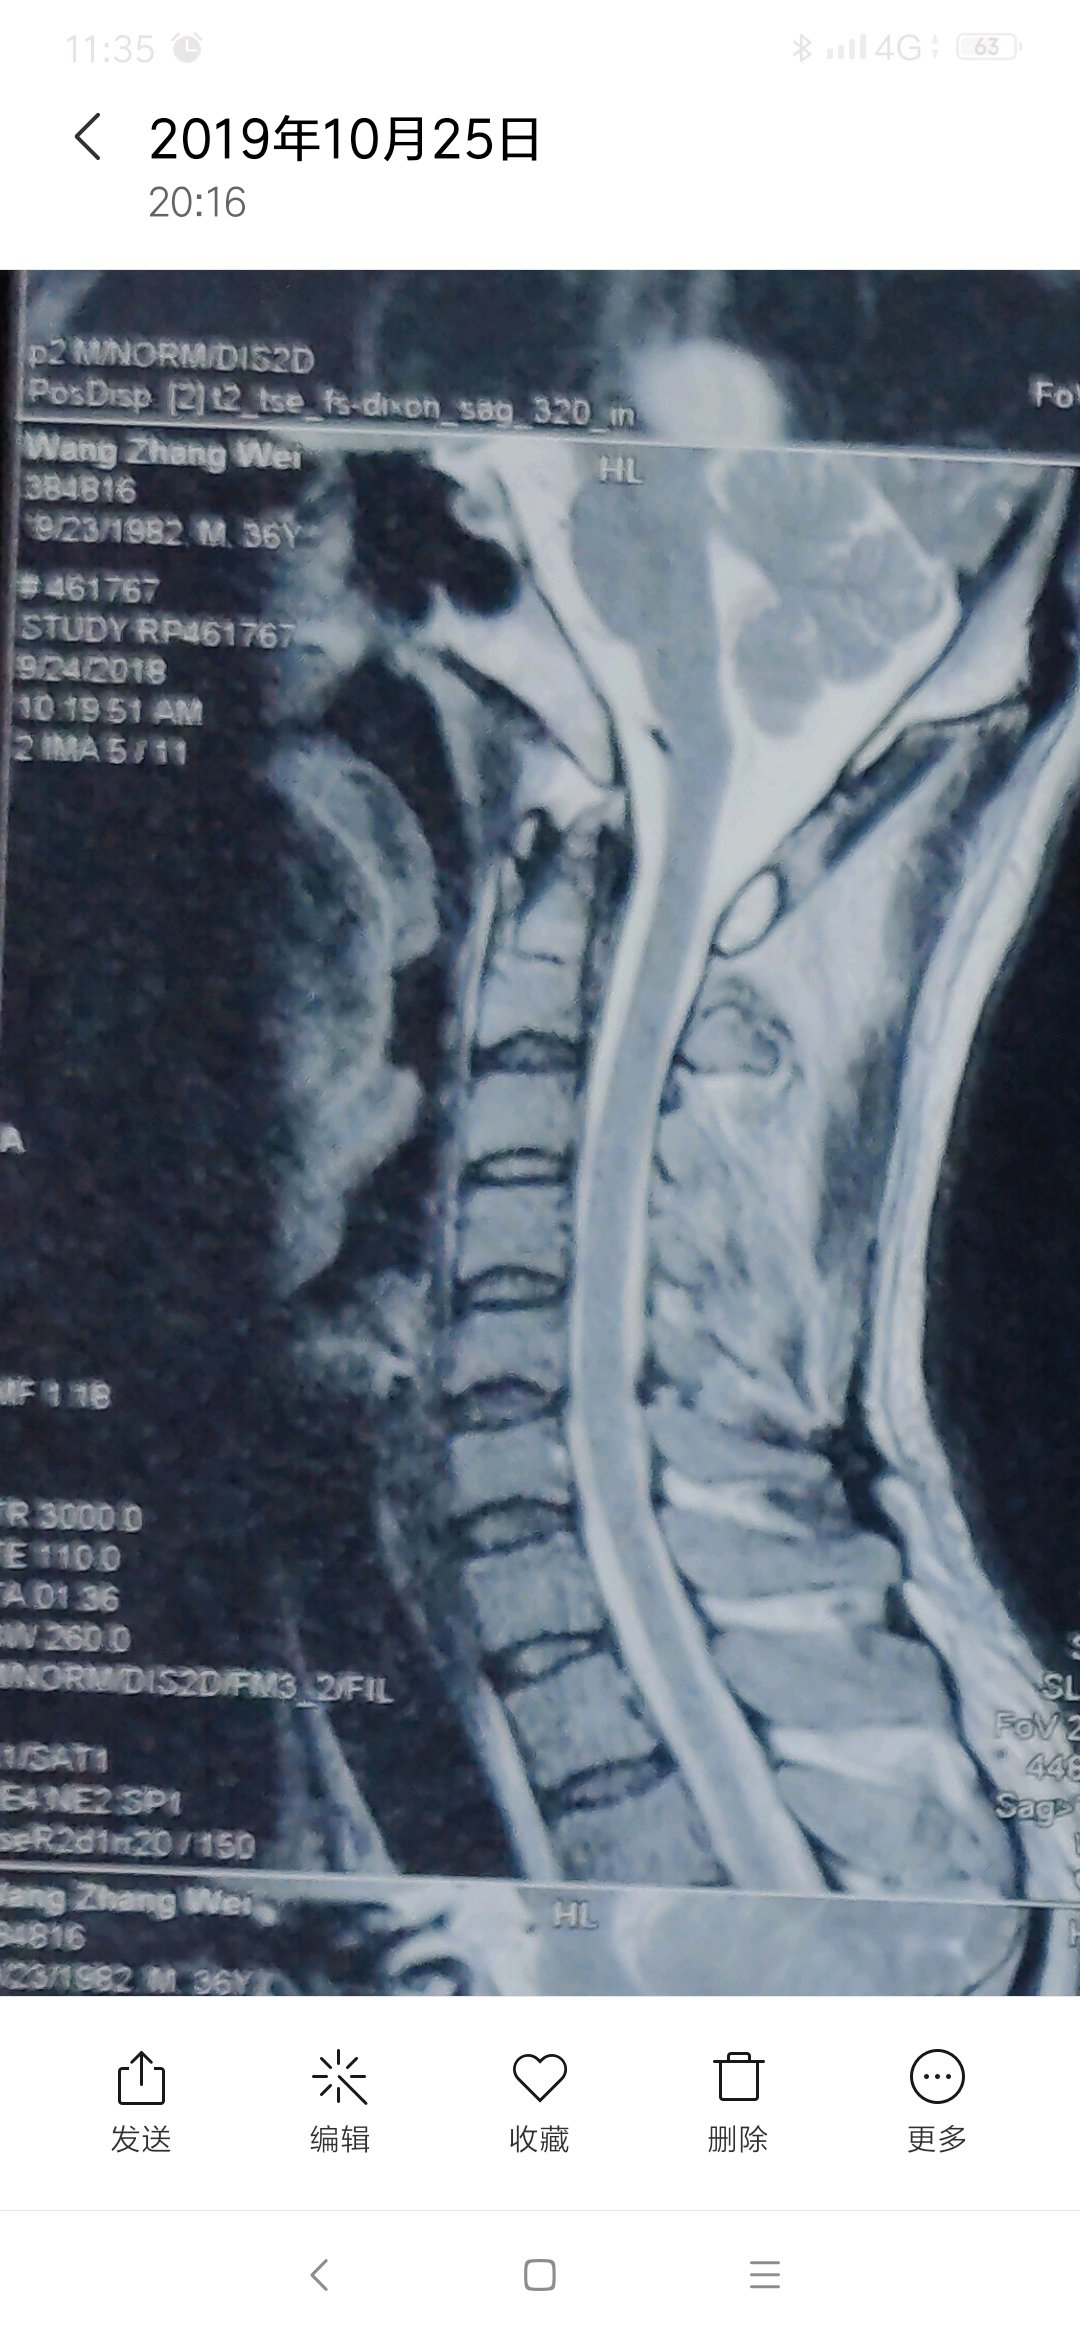

有专家吗,这个层度严重吗,怎么能治好,主要表现脖子疼痛,活动

有专家吗,这个层度严重吗,怎么能治好,主要表现脖子疼痛,活动受限。

片子不严重,多锻炼就好了

每次去医院看病,医院都说不严重,可是痛起来真的太痛苦了。